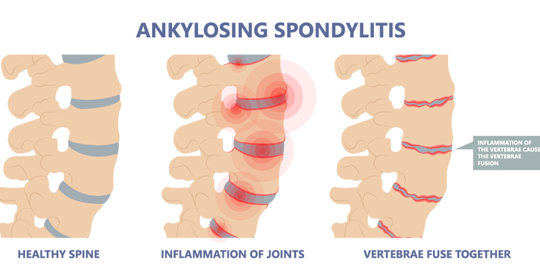

嬰兒痙攣:原因、症狀與處理方法

嬰兒痙攣:分類、原因及治療方法

嬰兒痙攣:治療與護理